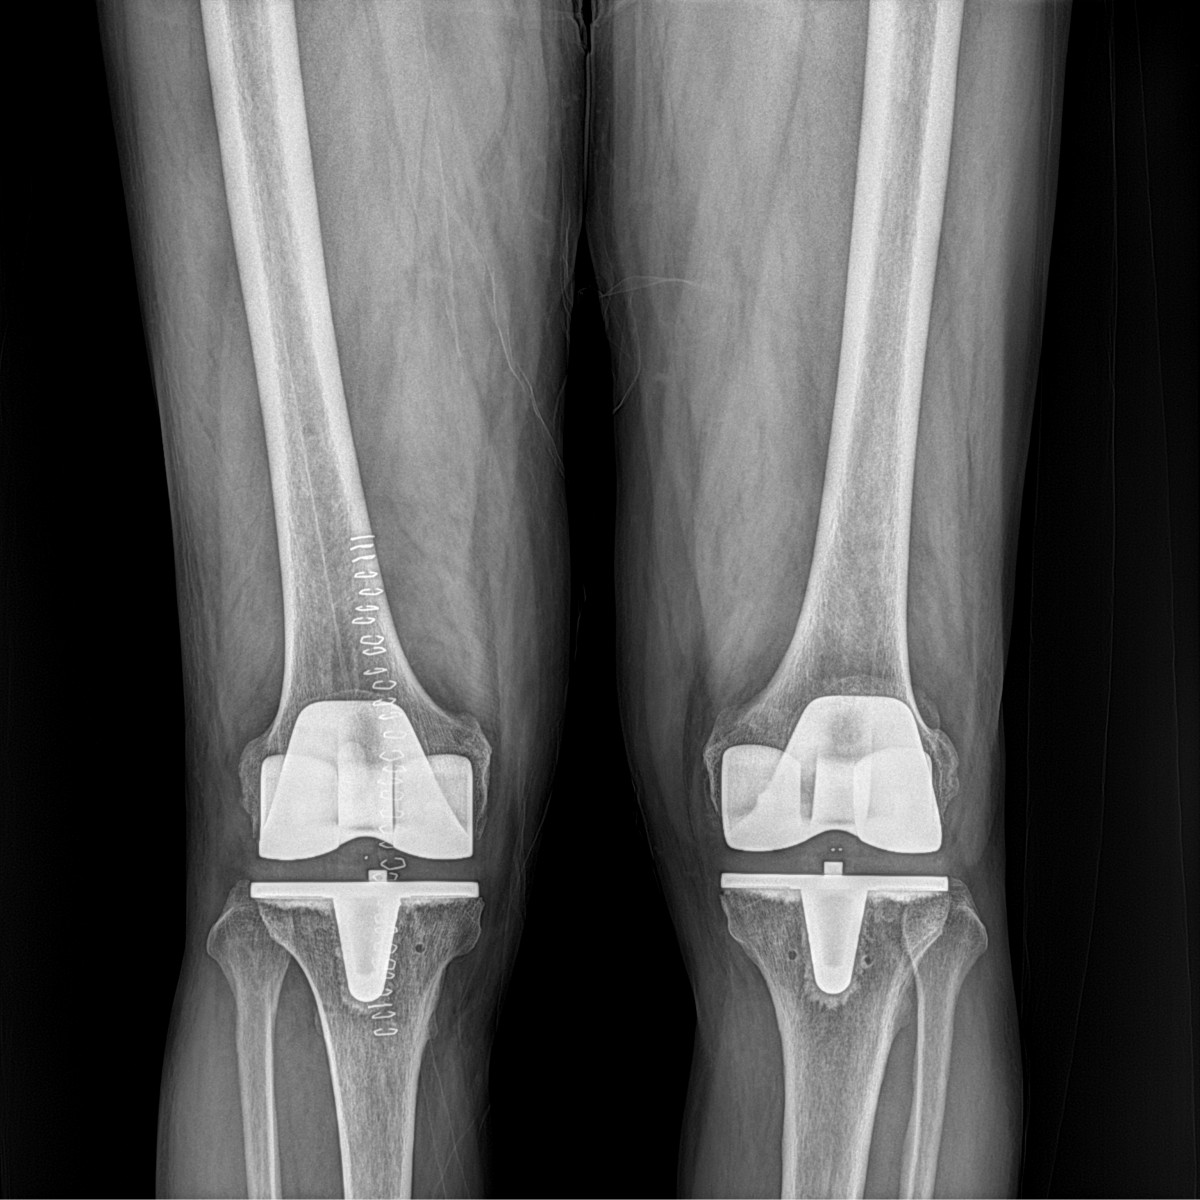

이재상원장님 무릎 인공관절 치환술 박용O 환자

dae765e4d9ac96aee867c9d6292d8784_1758010021_0747.jpg